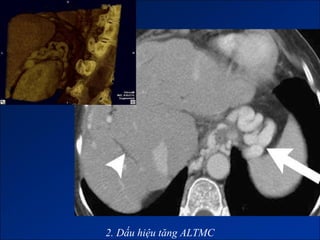

2. Dấu hiệu tăng ALTMC

2. Dấu hiệutăng ALTMC